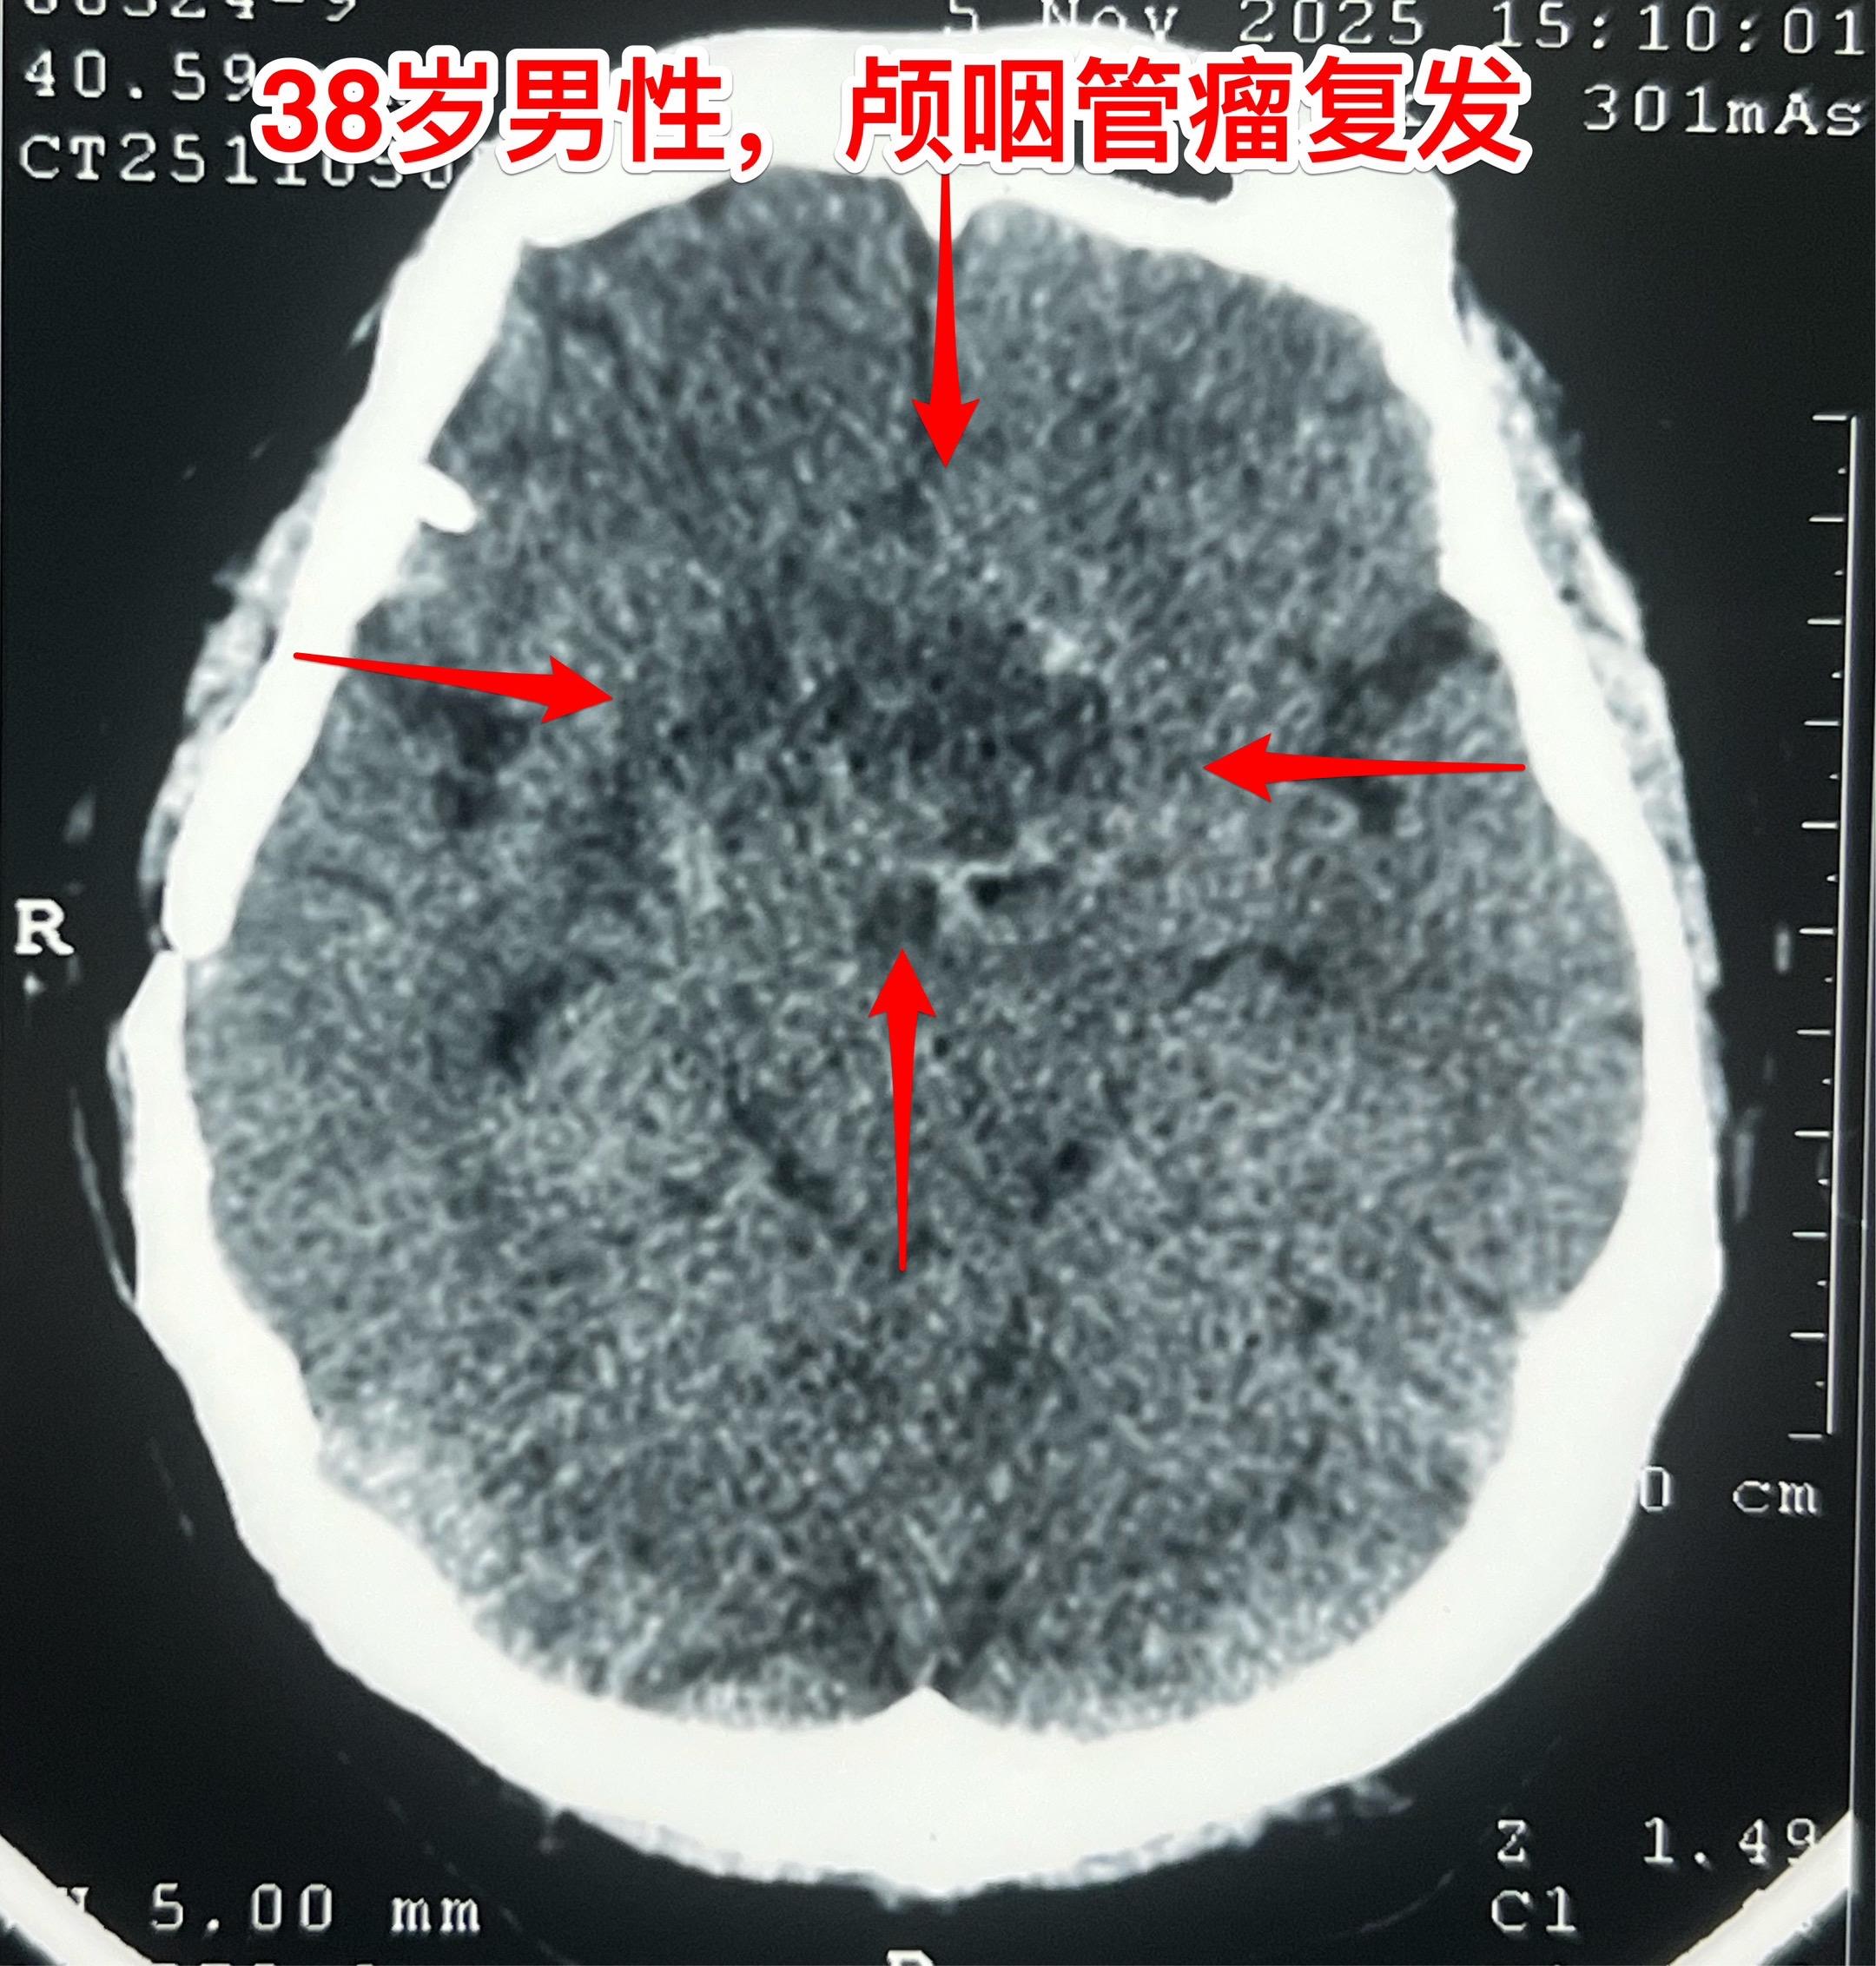

多次治疗后又复发的颅咽管瘤-不要轻易放弃。38岁福建男性,颅咽管瘤复发。 十年前因颅咽管瘤导致右眼几乎失明、右侧肢体无力,在上海行开颅手术切除颅咽管瘤,术后右眼完全失明。随后放疗一个月。2023年因颅咽管瘤复发在福建省某医院行经鼻内镜手术切除复发颅咽管瘤,肿瘤有残留。2025年5月仅有视力的左眼出现又视力下降,磁共振显示颅咽管瘤复发了,体积在增大。 病人患病十年,仍是未婚状态,家人的照顾是非常周到的。两个姐姐、两个妹妹和父母都在极力照顾他,这次得知肿瘤复发了,找到我,还是希